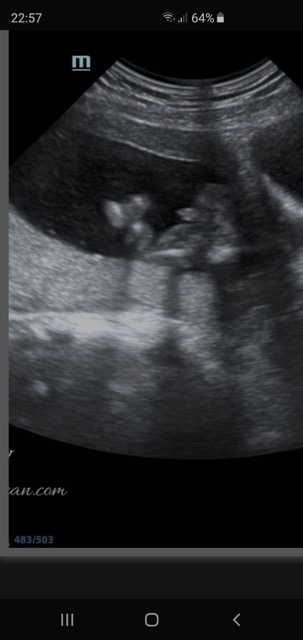

Gender predictions 💗💙

The first 3 are pictures of the baby and the last 2 I think are in between the legs 🤔 I’m not sure